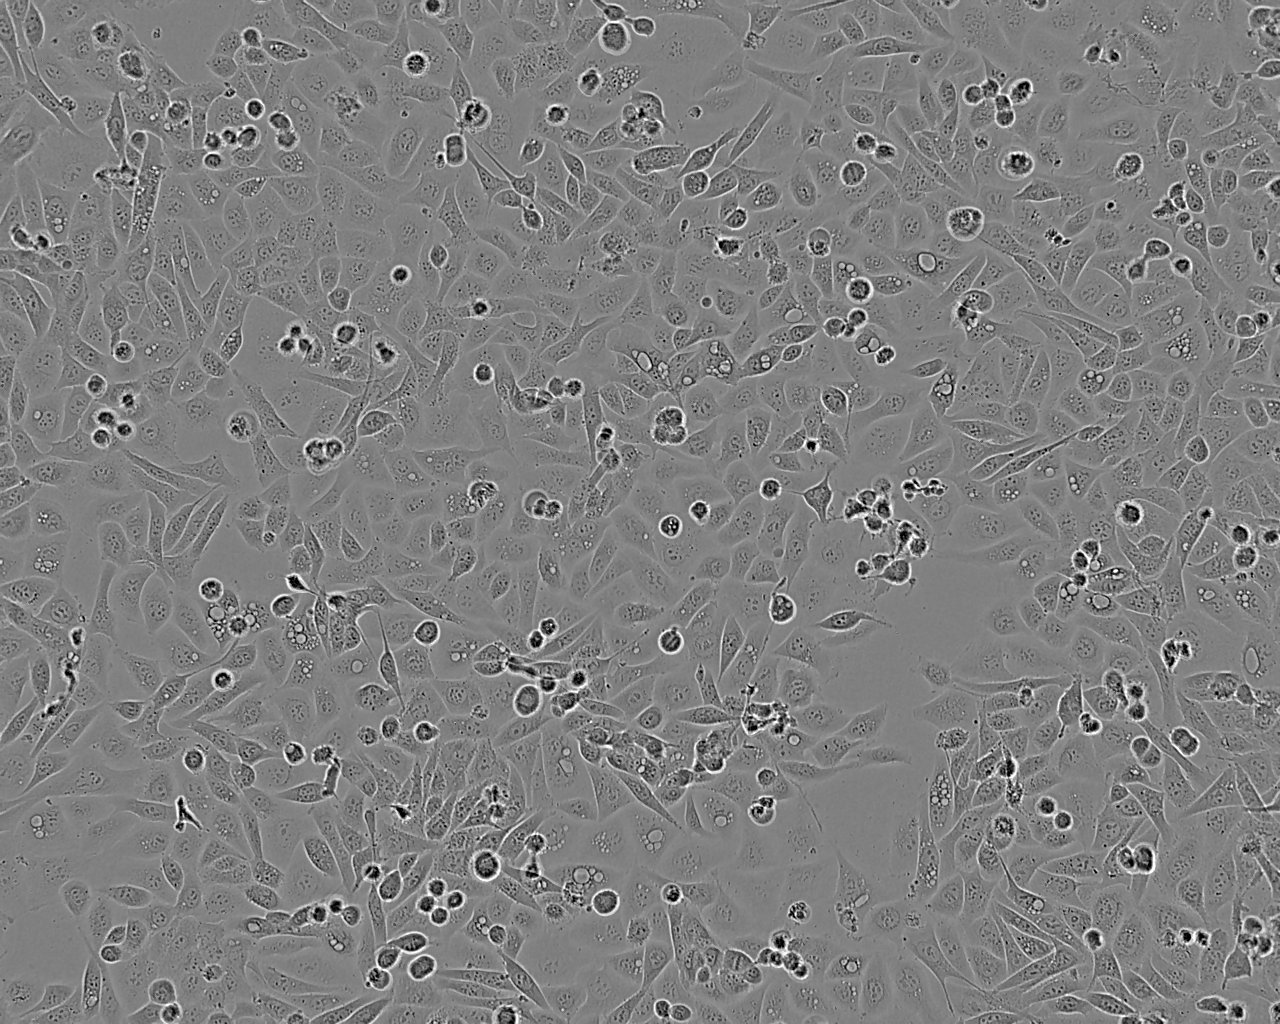

Images

Split sub-confluent cultures (70-80%) 1:4 to 1:8 i.e. seeding at 1-3 x 10,000 cells/cm² using 0.05% trypsin or trypsin/EDTA; 5% CO₂; 37°C. Saturation density approx 10⁵ cells/cm².

FLO-1 was established from a primary distal oesophageal adenocarcinoma in a 68 year-old Caucasian male in 1991. The Y chromosome could not be detected in this cell line by short tandem repeat (STR)-PCR analysis when tested at ECACC. It is a known phenomenon that due to the increased genetic instability of cancer cell lines the Y chromosome can be rearranged or lost resulting in lack of detection. The cell line is identical to the source provided by the depositor based on the STR-PCR analysis. Cultures derived from ECACC stocks of this cell line have been whole genome sequenced (Contino et al 2016) confirming the presence of many of the known mutations that drive oesophageal cancer